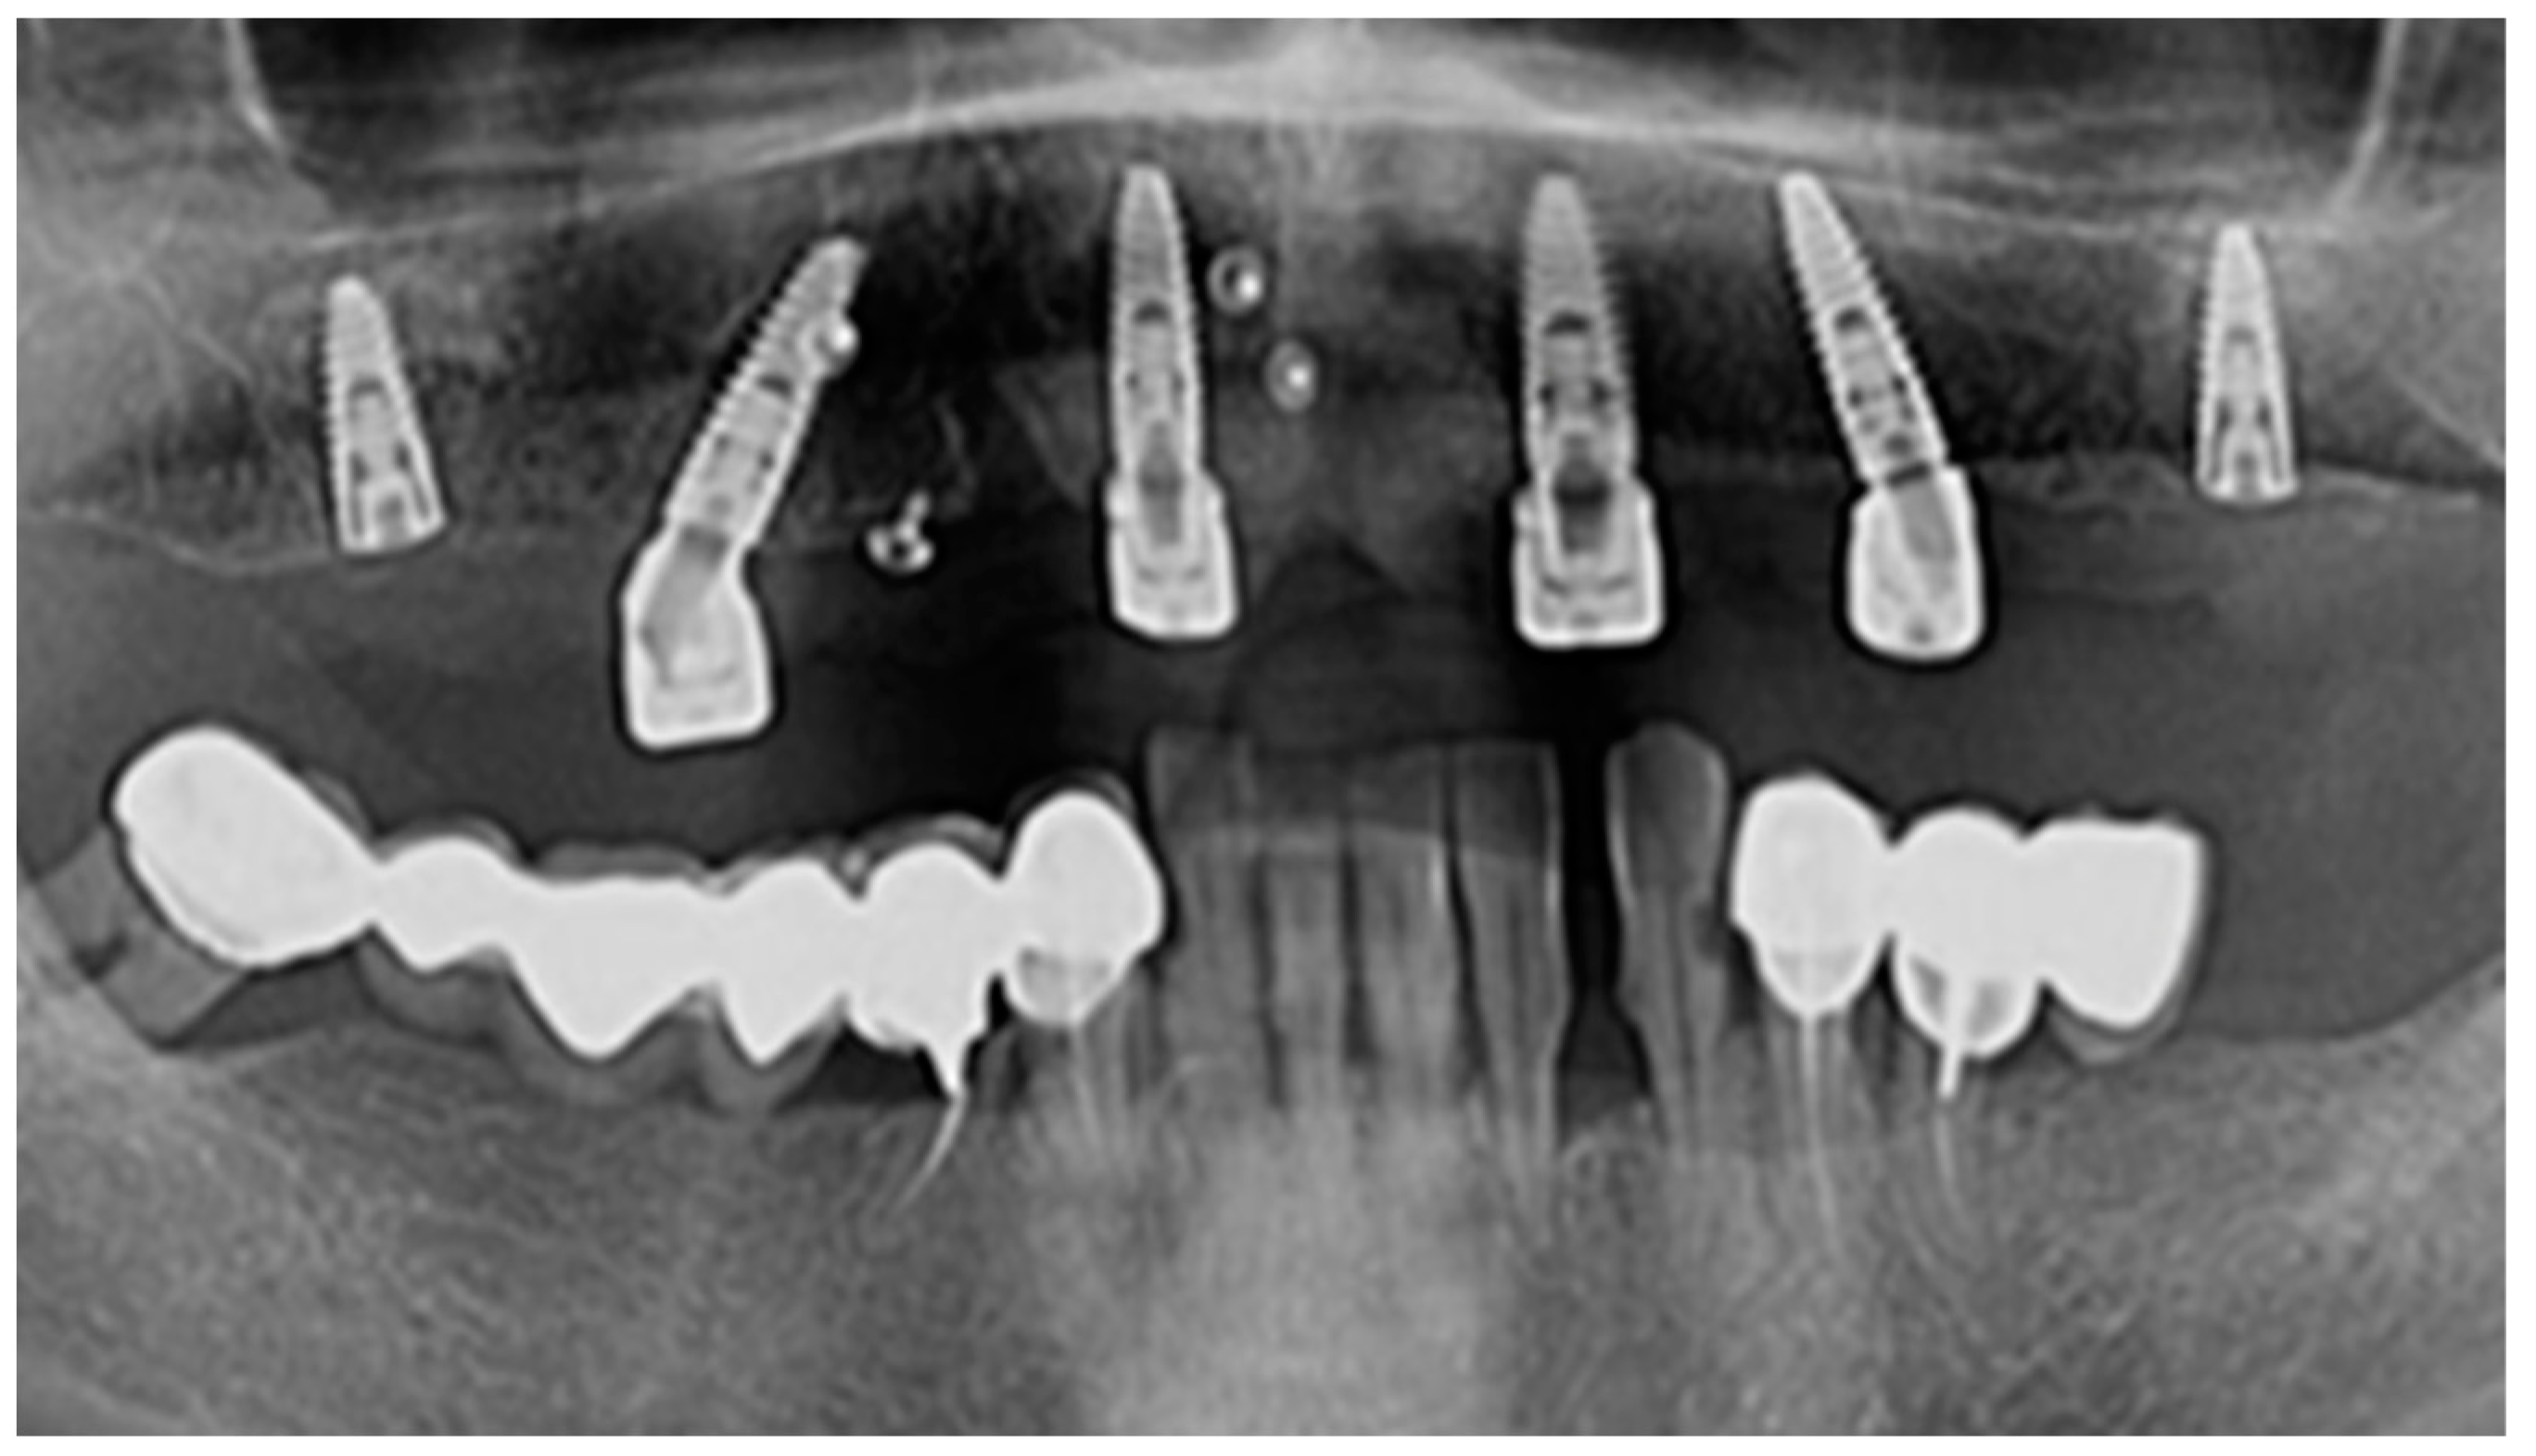

In the lateral areas of the jaws where the bone support was not enough, sinus lifting using BioOss (Geistlish Pharma AG, Baden-Baden Germany) and the resorbable membrane Bio Guide (Geistlish Pharma AG, Baden-Baden Germany) was used (Figure 2).

Figure 2.

Radiological examination of a bone augmentation clinical case.